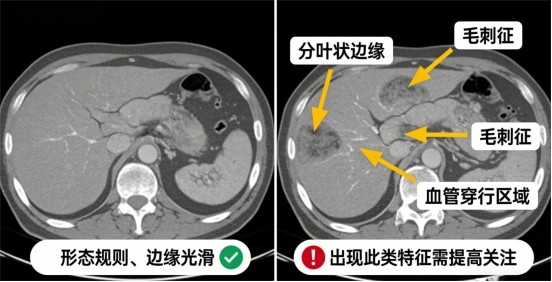

2. 看形态(关注CT报告描述)

若报告中出现以下表述,需提高关注:

·形态不规则、分叶状

·边缘有毛刺

·可见血管穿行或聚集